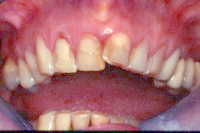

Ein 31 Jahre alter Patient zeigt einen starke Zahnfleisch-Rückgang im Oberkiefer (Abb. 1 und 3) und wir beschliessen, diese Rezessionen zu behandeln.

Der Erfolg der Behandlung ist deutlich in den Abb. 2 und 4 zu sehen. Sehr augenfällig konnte die Situation um den Eckzahn im linken Oberkiefer verbessert werden (vergleiche dazu Abb. 3 vorher und Abb. 4 nachher).